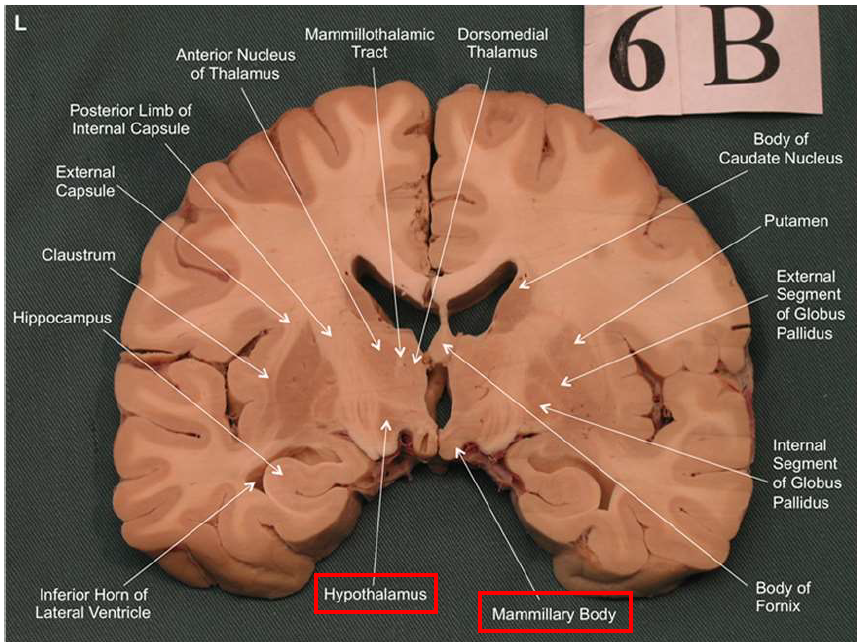

What is the fornix of the hippocampus?

Hippocampus output pathway (C-shaped)

Connects hippocampus to hypothalamus/mamillary bodies

Carries information to and from hippocampus

Important for memory consolidation and retrieval

What is this?

hippocampal fornix

Association areas activate the hippocampus, which reverberates in the Papez circuit until information is stored permanently

Hippocampus → fornix → mamillary bodies → anterior thalamic nucleus → cingulate cortex → hypothalamus